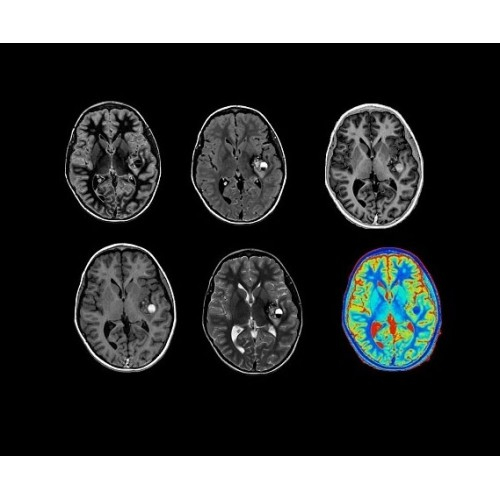

Стандартный пакет приложений SIGNA Works позволит вам достичь желаемых результатов в клинической практике благодаря набору высокоэффективных средств визуализации. Программные приложения, входящие в состав данных клинических пакетов, включают широкий спектр контрастов, функции обработки 2D- и 3D-данных, а также возможность коррекции артефактов движения. SIGNA Works предоставляет набор инструментов, необходимых для проведения эффективного клинического исследования.

• NeuroWorks — универсальное решение для визуализации анатомии головного мозга, позвоночника, сосудов и периферических нервов с четкой дифференциацией тканей.

• HyperWorks — пакет програмных приложений, который включает технологию HyperSense для поразительной визуализации и скорости.

• ImageWorks — повысит производительность МРТ благодаря визуализации высокого качества с MAGIC, четкими результатами пост-процессинга с READYView.

Технология полной оцифровки изображения Total Digital Imaging (TDI) предлагает потрясающие достижения в области визуализации:

• Технология Direct Digital Interface (DDI)использует независимый аналого-цифровой преобразователь для оцифровки сигнала от каждого из 128 радиочастотных каналов, что обеспечивает значительное увеличение качества за счет уменьшения фонового шума.

• Технология Digital Micro Switching (DMS)— это следующее поколение технологий радиочастотных катушек, основанное на замене аналоговых схем блокировки сверхбыстрыми микропереключателями (MEMS).

• Digital Surround Technology (DST)— это новая технология объемной оцифровки данных, которая объединяет сигналы от каждого элемента катушки. Прекрасное соотношение сигнал/шум и чувствительность поверхностных катушек в сочетании с превосходной однородностью и высокой проникающей способностью встроенной радиочастотной катушки — все это позволяет создавать качественные изображения не только позвоночника, но и всего тела.

• 48-канальная катушка TDI для головы, входящая в базовую комплектацию SIGNA Architect, обеспечивает феноменальную производительность с учетом особенностей каждого пациента. Благодаря гибкому и универсальному дизайну, высокому соотношению сигнал/шум и передовым технологиям визуализации, таким как HyperWorks, учитываются потребности подавляющего большинства пациентов.